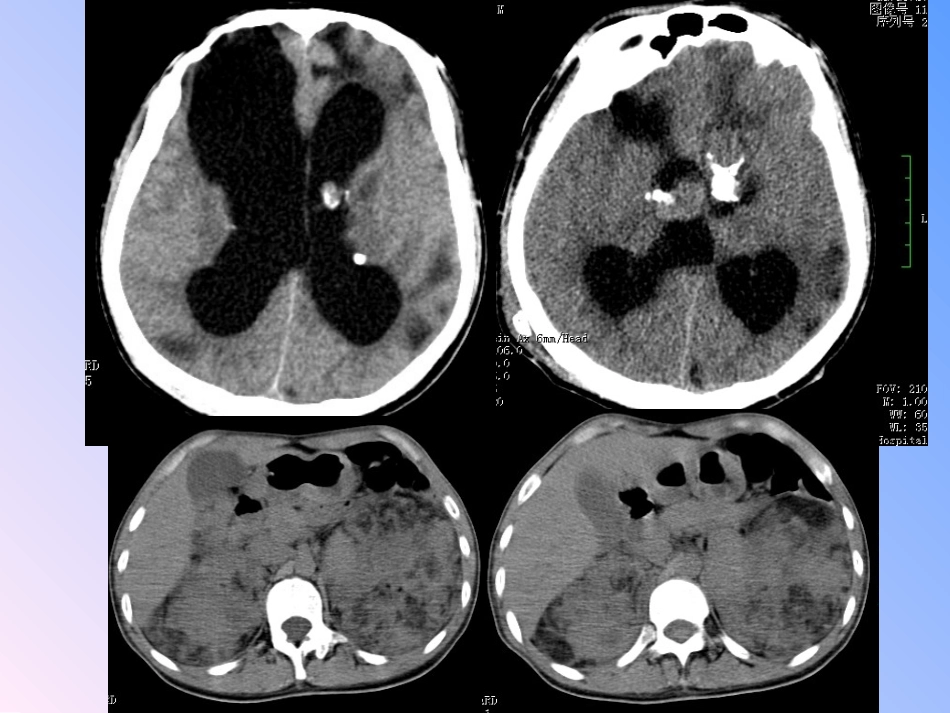

神经皮肤综合征病例1患者男24岁病史:以“意识不清半小时”为主诉入院,曾因脑积水手术。影像诊断:室管膜下巨细胞星形细胞瘤+双肾多发错构瘤。——结节性硬化综合征(TSC)病例2•患者女45岁•病史:气短3年,伴腹部不适1月影像诊断:室管膜下多发钙化结节+皮质下钙化结节+肺淋巴管肌瘤+双肾多发错构瘤+脊柱多发骨岛。——结节性硬化综合征(TSC)病例2神经皮肤综合征(又称斑痣性错构瘤病)指起源于外胚层的组织和器官发生的疾病,常导致神经系统、皮肤和眼同时受累,也可引起中胚层和内胚层的组织,如心、肺、肾、骨和胃肠等不同程度的损害,至今已报道40多种疾病,多数属于遗传性疾病。脊椎动物三胚层形成的部分器官最常见的神经皮肤综合征•Ⅰ型神经纤维瘤病(NF1)•Ⅱ型神经纤维瘤病(NF2)•结节性硬化综合征(TS)•脑颜面神经血管瘤病(Sturge—Weber综合征)神经纤维瘤病(NF)神经纤维瘤病(NF)是由于起源于神经嵴细胞异常所导致的多系统损害的常染色体显性遗传病,可分为两种类型:NF-1型是由于染色体17q11.2缺失所致,主要特征为:分布在脑神经、脊神经、皮肤或皮下组织的多发性神经纤维瘤,皮肤症状:以及表皮基底细胞内黑色素沉积而致皮肤色素斑(牛奶—咖啡斑)、雀斑、色素沉着。NF-2型是由染色体22q12.2缺失所致,主要特征为:双侧听神经瘤,常合并有脑膜瘤、脊膜瘤、星形细胞瘤以及脊旁后根神经鞘瘤,皮肤肿瘤以神经鞘瘤为主。Ⅰ型神经纤维瘤病(NF1)临表现床•(1)牛奶咖啡斑:大约占50%,常常在出生时即出现,开始数量少,颜色浅,随后数量逐渐增多,颜色加深。腋窝、腹股沟区的雀斑及色素沉着。•(2)Lisch结节:是由于眼球虹膜境界清楚的橙黄色圆形小结节(虹膜结节)。•(3)其他:蝶骨大翼发育不良、骨缝缺损、脊柱侧弯畸形、脑膜膨出,丛状神经瘤,颅骨和脊柱之外的肌肉骨骼病变等。牛奶咖啡斑Lisch结节(虹错构瘤)虹膜错构瘤(Lisch结节)•NF-1:皮肤牛奶咖啡斑等改变、骨骼畸形、神经纤维瘤或丛状神经纤维瘤,通常儿童期起病;图NF-1A:多发牛奶咖啡斑;B:雀斑伴牛奶咖啡斑;C:皮肤神经纤维瘤;D1:结节状神经纤维瘤;D2:丛状神经纤维瘤;D3:丛状及浸润性神经纤维瘤Ⅱ型神经纤维瘤病(NF2)•临床表现:NF-2型的临床表现即双侧听神经瘤,正常人群中发病率为1:50000,20左右岁出现。NF-2型患者皮肤病损表现不明显且不具有特异性,所以NF-2型在初诊时较迟。皮肤症状没有或很少。影像表现(1)双侧听神经瘤;(2)其他颅神经瘤如:双侧三叉神经瘤、双侧副神经瘤;(3)脑膜瘤;(4)脊柱及脊髓表现(髓内室管膜瘤,多发脊膜瘤,椎间孔扩大等)双侧听神经瘤:大多数听神经瘤表现为以内听道为中心占位病变,与岩骨呈锐角,其边界清楚。CT表现为桥小脑角区类圆形肿块,密度较均匀,病灶较大者可挤压小脑、脑干使之变形,可伴有囊变出血,钙化少见,增强后实质部分明显强化,骨窗可见内听道扩大或正常;MRI表现为T1WI低、等信号,T2WI稍高信号,病灶内出现囊变出血信号可不均匀,增强后强化明显。小听神经瘤仅依靠平扫很容易漏诊,应常规MRI增强扫描,表现为听神经束增粗,明显强化。多发脑膜瘤:可发生于颅内任何位置,大多余硬模呈宽基底相连,也可发生在脑室内,T1、T2表现余脑实质等信号的信号强度,若不做增强容易漏掉。有明显占位效应,周围可有不同程度的水肿,增强明显强化,伴脑膜尾征。双侧听神经瘤,多发脑膜瘤脑室内脑膜瘤神经纤维瘤病的诊断标准●符合下列2条或2条以上者即可诊断NF-1型:(1)6个及以上直径>5mm的皮肤咖啡牛乳色斑;(2)2个及以上任何类型的神经纤维瘤或1个丛状神经纤维瘤;(3)腋窝或腹股沟区雀斑;(4)视神经胶质瘤或其他脑实质胶质瘤;(5)2个及以上虹膜错构瘤(Lisch结节);(6)特征性的骨性病变,包括蝶骨发育不良,假关节或长骨骨皮质变薄;(7)直系一级亲属中有NF-1型家族史。●有以下任何1种异常表现的即可诊断为NF-2型:(1)CT或MRI显示桥小脑区肿块(无需组织学依据);(2)患者直系亲属并以下疾病的任意两种表现:神经纤维瘤、脑膜瘤、胶质瘤、施万细胞瘤(神经鞘瘤)、青少年晶状体后包膜下混浊。结节性硬化症•结节性硬化(TS)以常染色提...